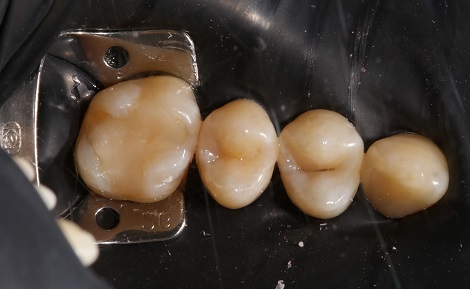

Якісно запломбовані кореневі канали є основою довговічності. Тому очищення і пломбування кореневих каналів в «Домі Стоматології» приділяється особлива увага! Після пломбування кореневих каналів проводиться контроль якості пломбування за допомогою знімка.